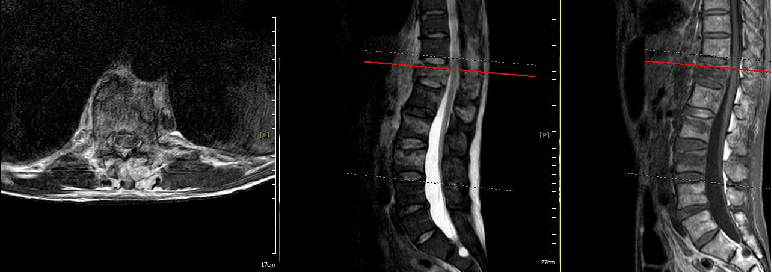

三、MRI:鉴别新旧骨折的 “时间侦探”

新鲜骨折“验真仪”:

新鲜骨折(<4 周)在 MRI 的 STIR 序列(抑脂像)上表现为高信号(“亮白色”),提示椎体骨髓水肿、骨折活动性炎症。 -

陈旧性骨折无明显水肿信号,呈低信号或等信号,此时手术止痛效果可能不佳,需优先保守治疗。 -

排除脊髓压迫:T2 加权像可显示椎间盘突出或血肿是否压迫脊髓,避免漏诊需急诊手术的危重症。

68 岁的李爷爷腰背痛 2 个月,X 线显示T11、L2压缩改变。MRI 发现T11 为陈旧性骨折(无水肿信号),L2 为新鲜骨折(高信号),最终仅对L2行手术治疗,避免了对 “老骨折” 的无效干预。